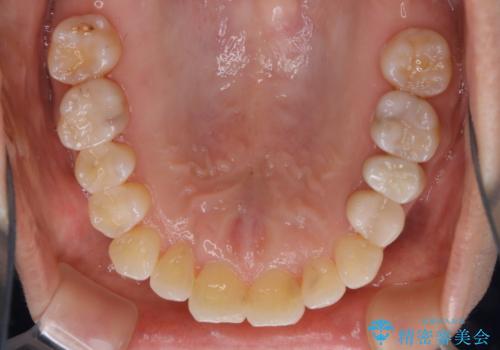

矯正治療とセラミック治療が終了後のPMTC

- 矯正治療とセラミック治療の総合治療が終了したため、クリーニングをしっかりとしてからメンテナンスに入りたいとのことでした。PMTC30分コースを行いました。

矯正治療が終わり、せっかくきれいになった歯並びも、虫歯・歯周病などになってしまっては元も子もありません。

矯正治療やセラミックなどによる被せ物の治療終了のタイミングではクリーニングを行い、汚れや着色の除去、歯と歯の間・歯と歯肉との境目などのケアをしっかりすることをおすすめしています。

ご自身での歯ブラシ・セルフケアを行うと同時に、定期的なクリーニング(PMTC)を行うことで、いつまでも健康な歯を保つことができます。